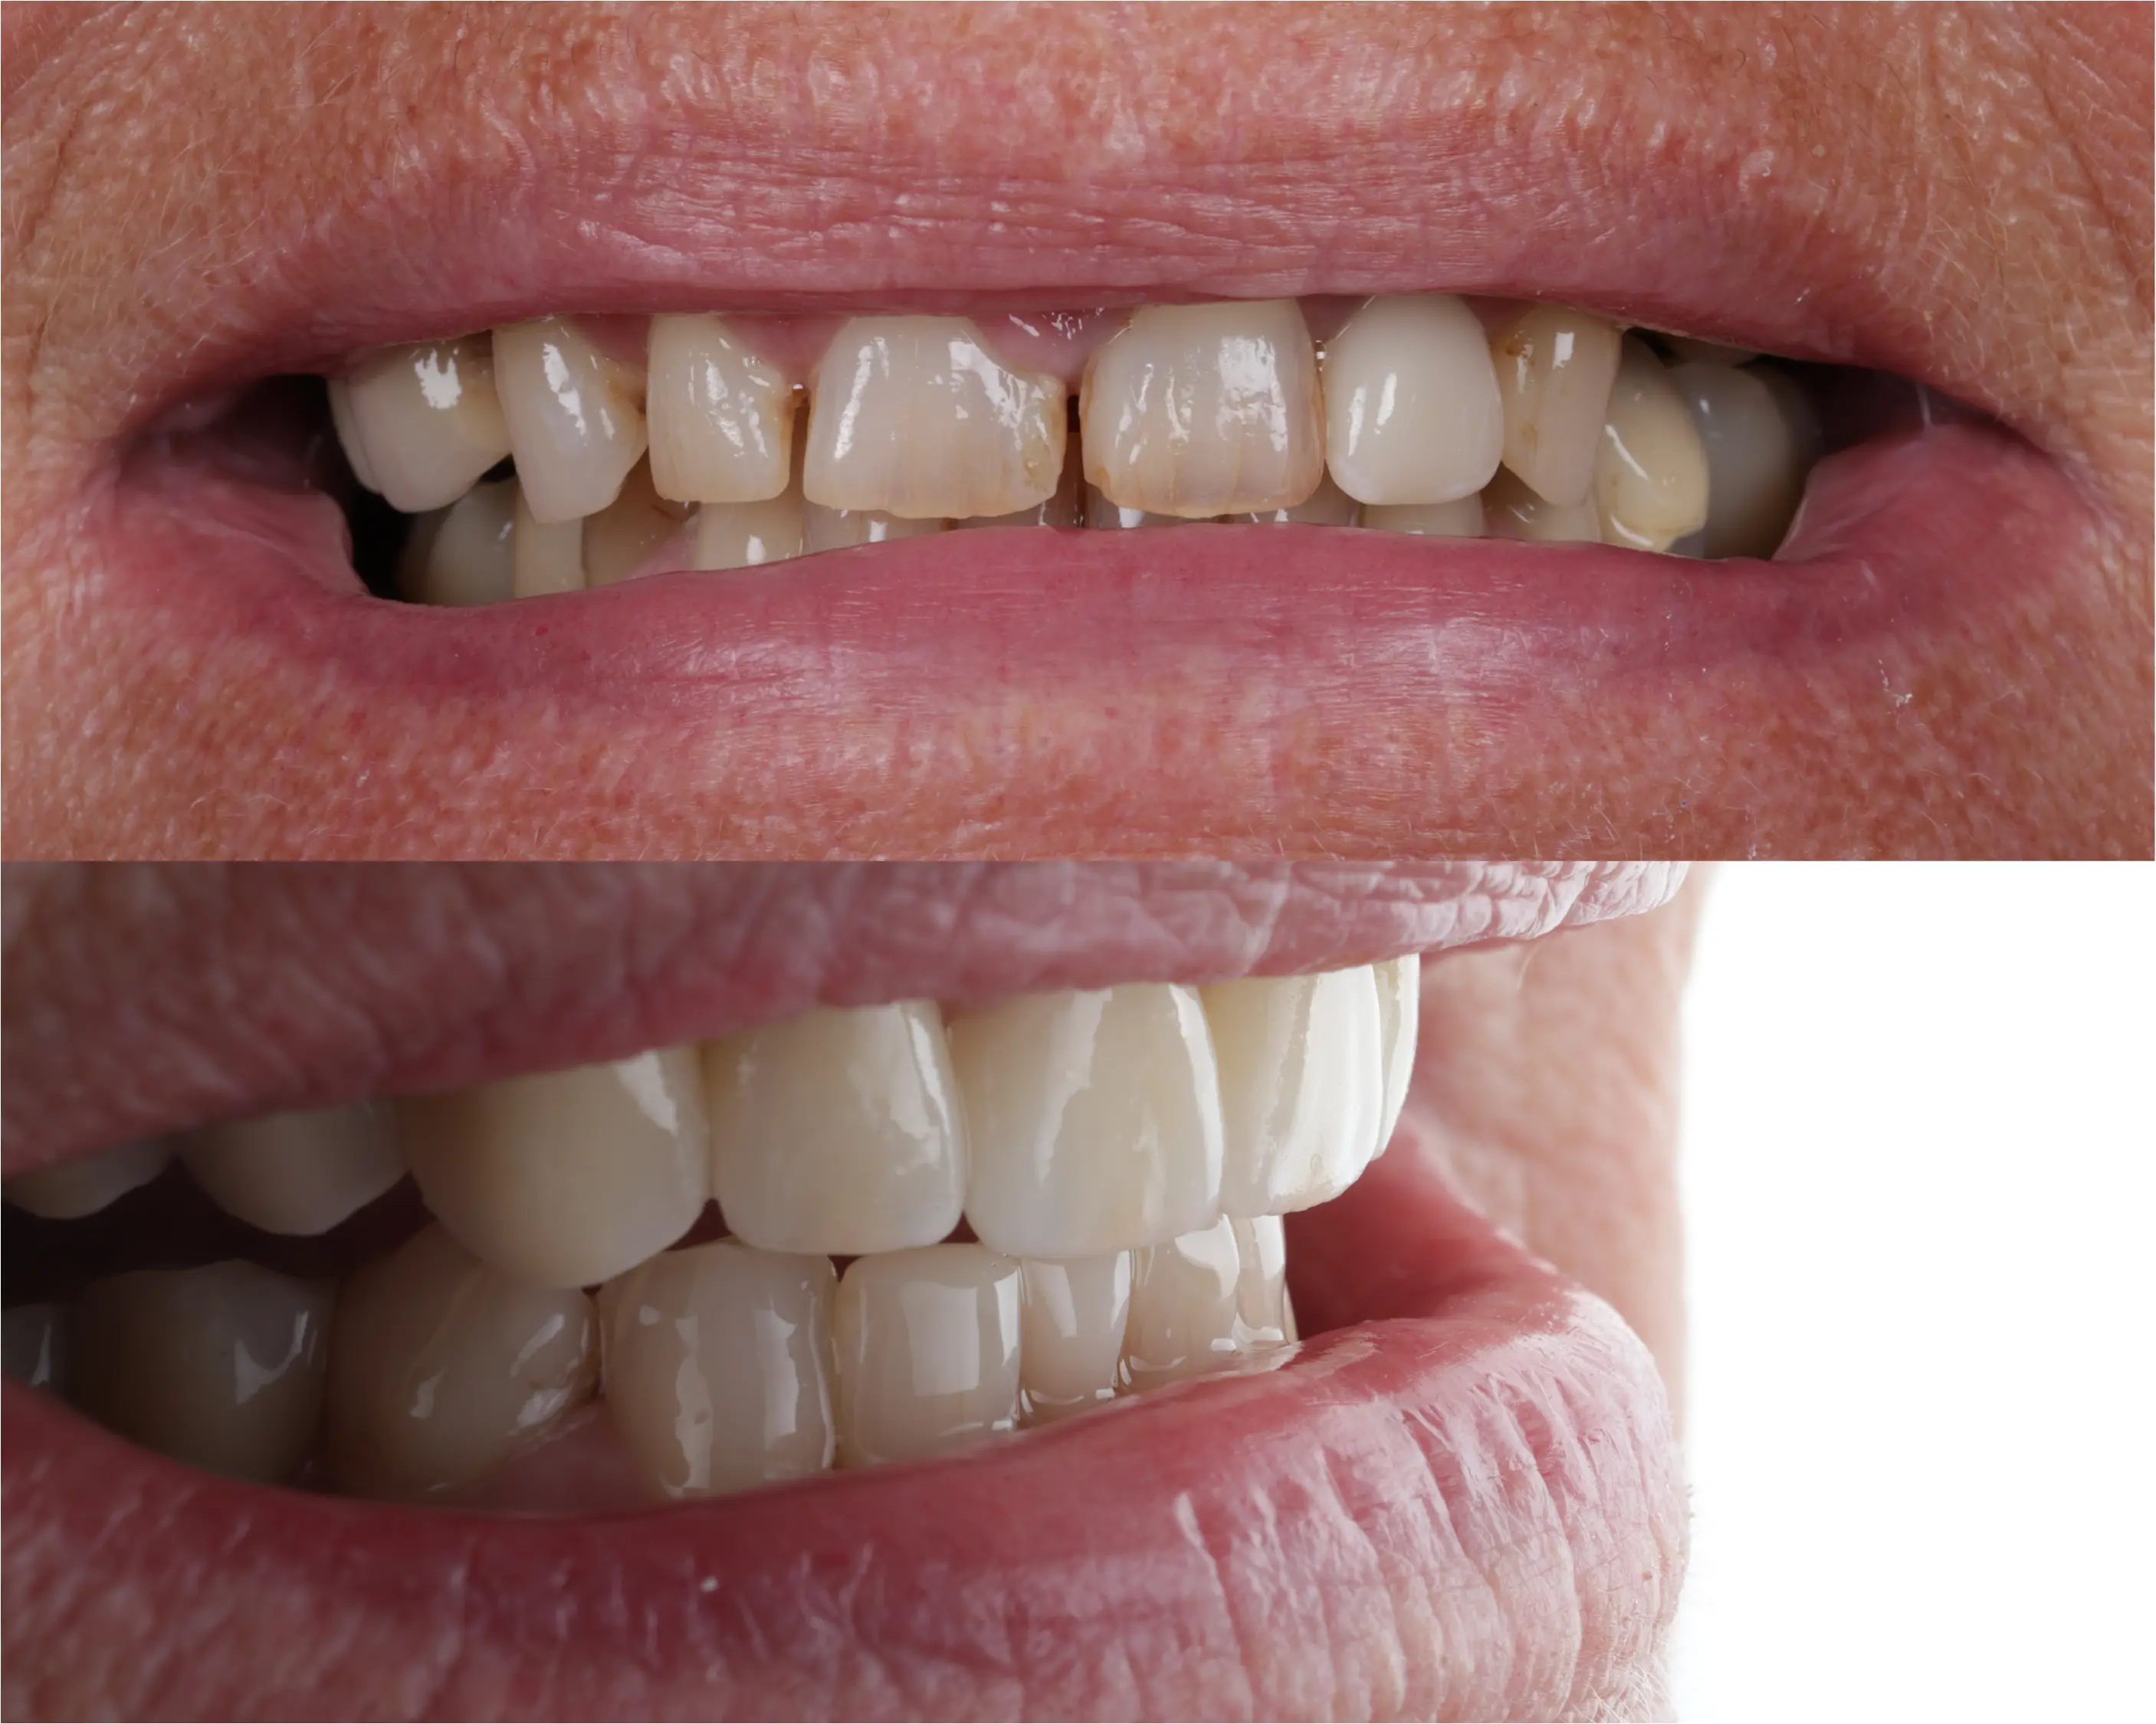

Denne 57-årige kvinde kom til os med et ønske om et smukkere smil og en mere velfungerende tyggeevne, da hun manglede flere tænder i overkæben. For at skabe balance og funktion blev biddet hævet med en kombination af plast og porcelæn. Derudover har vi lavet broer på implantater i begge sider af overkæben samt tre nye kroner i underkæben. Resultatet er et naturligt og harmonisk smil – og en markant forbedret tyggefunktion, der gør hverdagen lettere og mere behagelig.